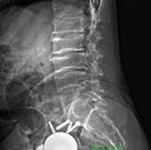

Resim 2.

- Radyolojik Bulgular

2. Epifizyal değişiklikler: Uzun kemiklerin epifizlerinde irregular yapı, morfolojisi bozulmuş epifizler.

Femur başında: Kısa femoral boyun, coxa vara, kalça çıkığı veya düzensiz epifizyal konturlar.

3. Ek bulgular: Omurga büyümesi normal doğumdan sonra başlar, ancak ergenlik öncesinde yavaşlar.